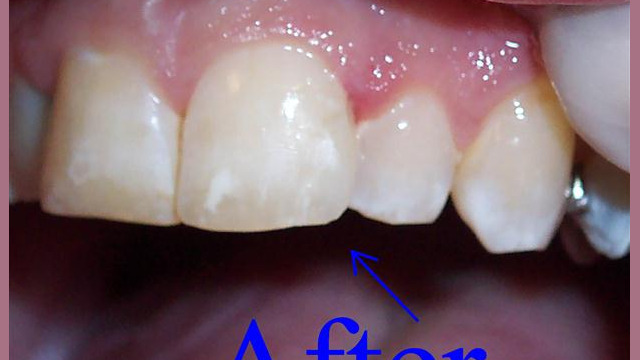

Dental Bonding

Cosmetic Dentistry

Ready to restore beauty, brightness, and luminescence to your smile? Our cosmetic dentistry services are designed to do just that! Our staff will work with you to determine which treatments best fit your needs and goals for your smile.